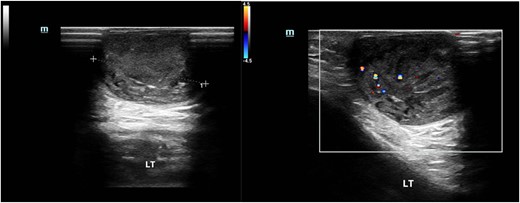

An 83-year-old man was admitted to our hospital with a skin lump on the incision located on the left knee without other concomitant symptoms (Fig. 1). He received left total knee arthroplasty 3 years ago. A mass, the size of a grain of rice, appeared on the incision 1 month after operation. Within 3 years, the mass gradually increased to the size of a pigeon egg. Physical examination revealed a skin-like, ~3 × 3 × 2 cm cystic solid mass with a clear boundary, a soft texture and painless touch, protruding on the skin surface. Laboratory data showed that inflammation index and tumor series index were normal. Ultrasonography (US) shows a 2.5 × 2.5 × 1.6 cm heterogeneous hypoechoic mass with regular borders (Fig. 2).

Ultrasound image of the epidermal cyst. US shows a 2.5 × 2.5 × 1.6 cm heterogeneous hypoechoic mass with regular borders.